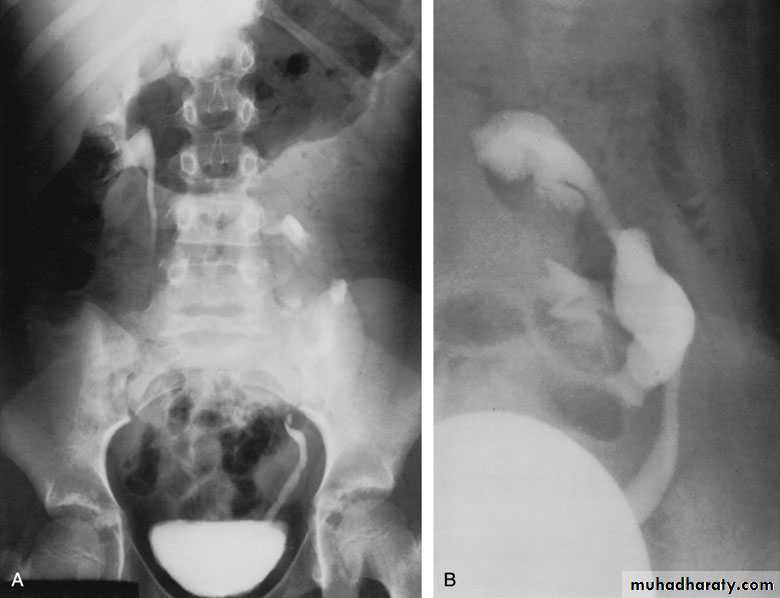

Ureteral duplication: partial and complete

Partial duplication: is more common. Two ureters draining single kidney for variable length, then unite together before entering the bladder in one ureteric orifice. Rarely the lower part is duplicated as inverted Y ureter.Complete duplication:

Less frequent, the whole ureter is duplicated, and each one opens in separate orifice in the bladder. The ureter draining the upper partopens more distally

in the bladder.

Bifid renal pelvis

iComplete ureteral duplication and ectopic ureteric orifice.